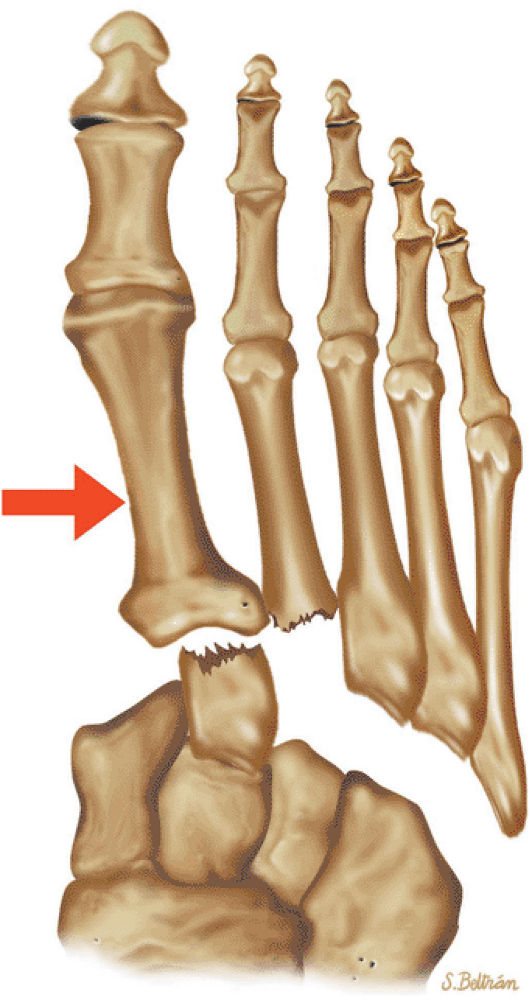

arthrosis at the tarsal-metatarsal joints in particular should prompt a careful search for Lisfranc fracture—dislocations in the axial plane.